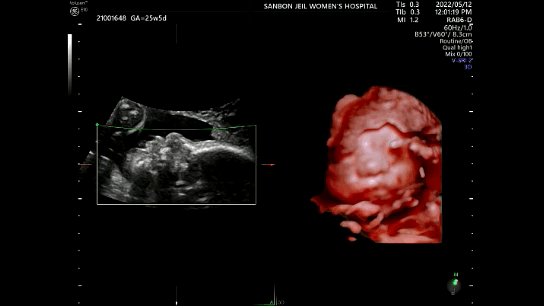

23주 2일차 2차 정밀초음파 이후 5D 정밀초음파를 예약하고 오늘 진료를 보기 위해 병원을 다녀 왔다. 25주 5일차에 받게된 5D 정밀초음파와 임당검사를 받게된 과정을 기록하도록 하겠다.

주수가 더 지날수록 아기 얼굴이 잘 안보인다고 하여 25주에 받게된 5D 정밀초음파. 호띵이의 얼굴을 입체적으로 볼 수 있다고하여 설레는 마음으로 예약한 시간에 맞게 초음파실에 들어가게 되었다.

호띵이의 자세가 매순간 바뀜에 따라 얼굴보기가 어려웠다. 그리고 얼굴에 계속 손을 가져다대서 온전하게 얼굴을 볼 수 있었던 순간이 많지는 않았다. 위의 사진은 그나마 얼굴이 제일 잘보이는 순간을 잘라서 편집을 했다. 호띵이 모습을 보면 엄마 얼굴을 닮은 거 같은데 어떤 부분은 또 나를 닮은거 같기도하고 어쨌든 사랑스러운 아기다.

초음파 영상에서 입에 손을 갖다대는 것과 하품하는 장면도 보았고 뱃속에서 쉴새없이 자세를 바꾸는 것도 보았다. 초기에는 얌전했던 호띵이가 커감에 따라 활발히 움직이는 걸 보니 약간 뭔지 모를 뿌듯한 감정도 느껴졌다.

위의 6가지를 약 30분가량의 초음파를 통해 확인하였다. 오래 걸렸던 이유는 온전히 얼굴을 다 확인하기 위해서였는데 호띵이가 얼굴을 안보여주려해서 시간이 걸렸다. 1번째 초음파를 15분가량 진행하고 얼굴을 다 보지 못해 잠깐 나가서 병원내에 걸어다닌 후 2차 초음파 15분가량을 통해 확인해야할 것들을 최종 확인하였다.

손가락과 발가락은 5개씩 다 잘 자라고 있었고 귀도 잘자라고있었고 눈도 살짝뜨는것도 보았다. 심장박동수도 주차에 맞게 150bpm의 속도로 잘 뛰고 있었다. 실질적으로 정밀초음파는 이번이 마지막이라고 해서 호띵이 얼굴 제대로 보고싶었는데 부끄러움이 많고 활발하게 움직이는 아기라 그런지 매번 얼굴에 손을 가져다대는 바람에 얼굴을 다 보지는 못하였다.